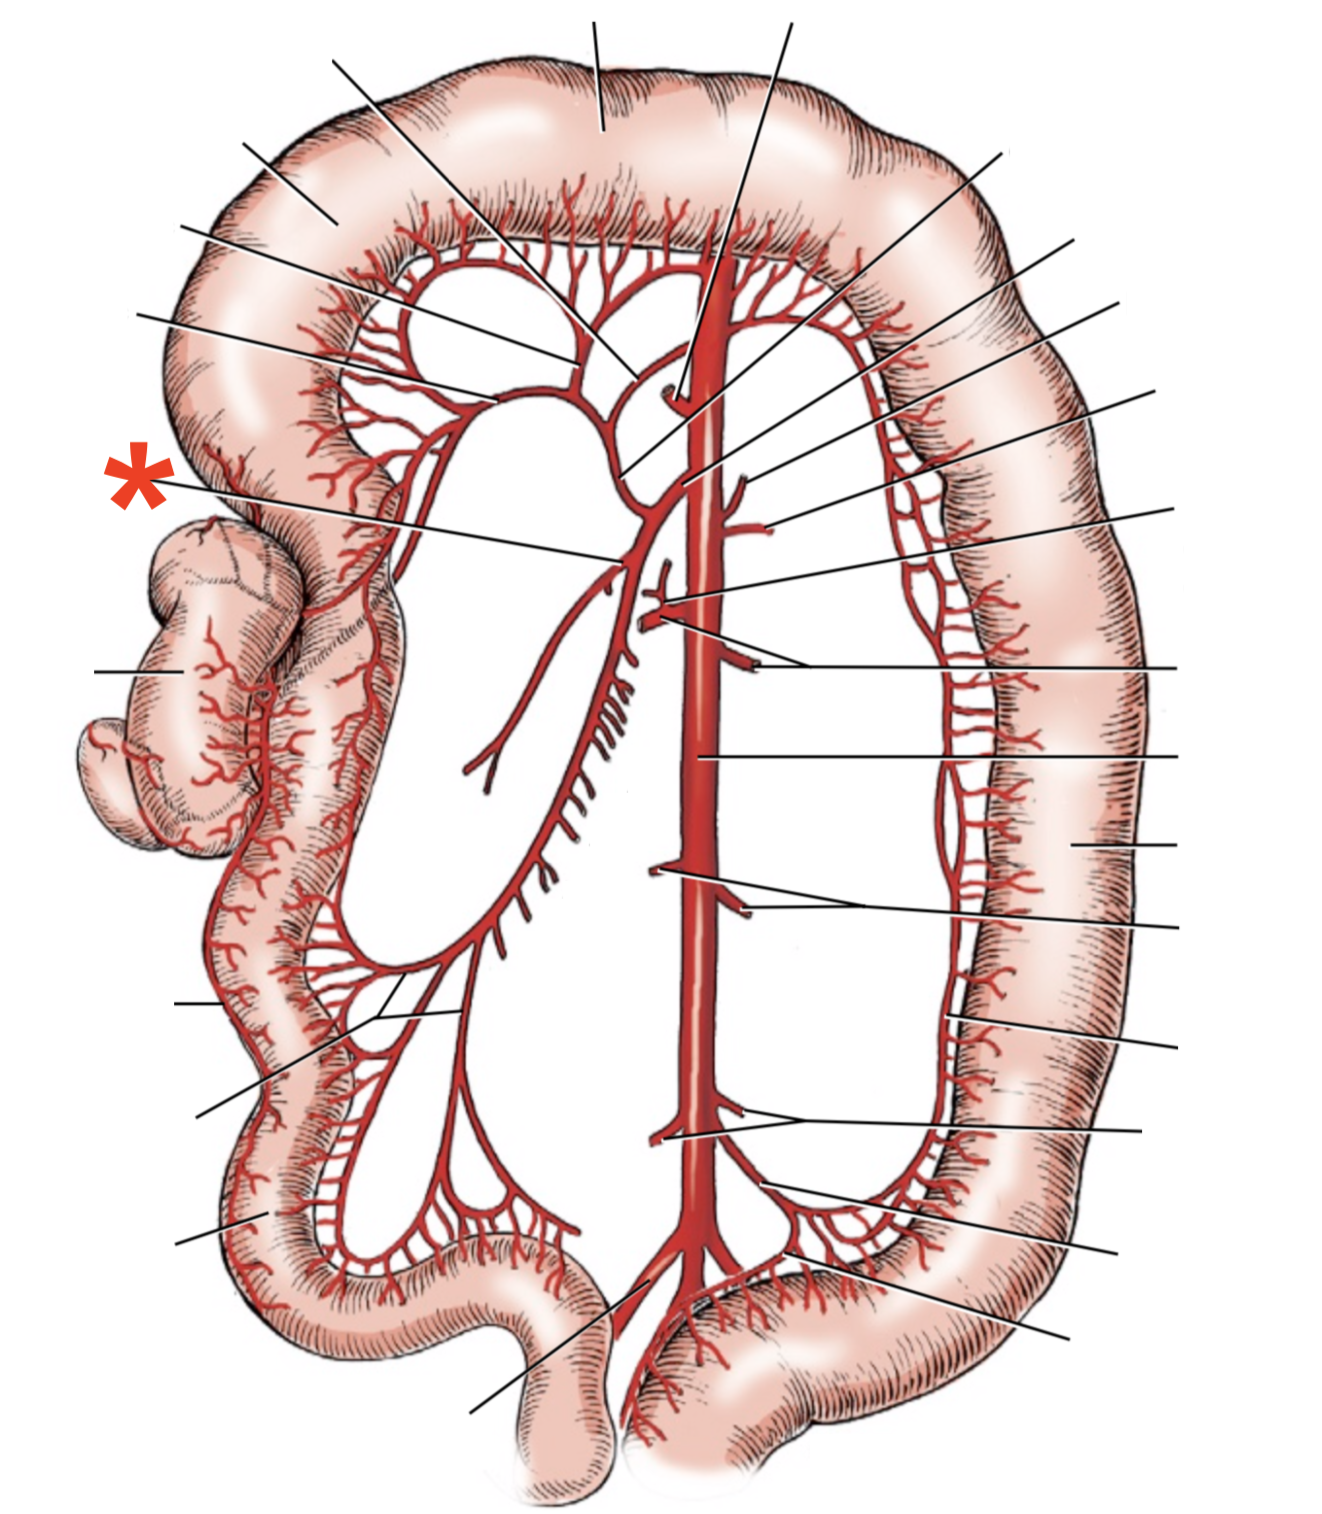

A

A. mesenterica cranialis

15

Q

A

A. pancreaticoduodenalis caudalis

16

Q

A

Aa. jejunales

17

Q

A

A. ilei

- Anastomises with r. ileus mesenterialis a. iliocolica

18

Q

A

A. ileocolica

19

Q

A

A. colica dextra

20

Q

A

A. colica media

21

List the branching of *a.* *mesenterica* *caudalis*

* *A. colica sinistra*

* *A. rectalis cranialis*

List the branches of *a.* *mesenterica* *cranialis*

* *A.* *pancreaticoduodenalis* *caudalis*

* *Aa. jejunalis*

* *A. ilei*

* Common trunk

* A. colica media

* A. colica dextra

* *A. ileocolica*

* *R. ilei mesenterialis*

* *A. cecalis*

* *R. colicus*